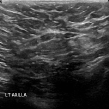

Hence, the dataset used in this work consisted of 537 and 360 with benign and malignant tumors, respectively. The whole dataset was shuffled randomly, and then split, in a stratified fashion, in two subsets, with 630 images for training and validation, and 269 for testing. A sample of benign and malignant BUS images is shown in Fig. 2.

Inception V3 only reaches the values of 0.756 and 0.783, respectively in the test dataset. However, during the training, it reaches accuracy values over 0.93 and AUC of 0.89 which implies that the model is over-fitting. Normalization techniques, such as Dropout and normalization, may help to reduce the over-fitting issue and improve its performance in the testing stage [17]. A deep exploration of the hyperparameters choice such as the batch size, the learning rate, the number of layers to be retrained (for the case of fine tuning), the size of the fully connected layers and number of layers (for the case of feature extraction) and the use of normalization methods is needed to be carried out. As is it possible to see from the sample of results show in Fig. 4 the variability of the content in the images affects the predictions made by the network. This may could be tackled by using different data augmentation methods which can generalize the variability of this kind of data.